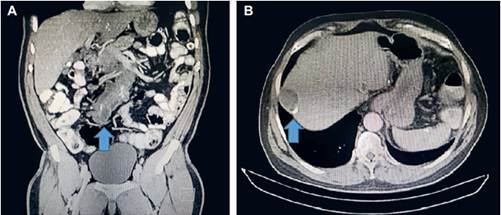

La endoscopia digestiva alta informó hernia hiatal de 2 cm, gastritis eritematosa antral sin evidencia de atrofia, metaplasia intestinal o displasia. La colonoscopia fue reportada como normal. La tomografía computarizada (TC) de tórax y abdomen mostró masa tumoral en la raíz del mesenterio, nódulos hipodensos de paredes calcificadas, hacia el hemiabdomen inferior derecho de contornos lobulados de 9 x 9 cm, y otra localizada en la región pre-rectal de 38 mm, un nódulo hipodenso hepático del segmento VIII, de 43 x 30 mm con pared calcificada, y colelitiasis múltiple (Figura 1).